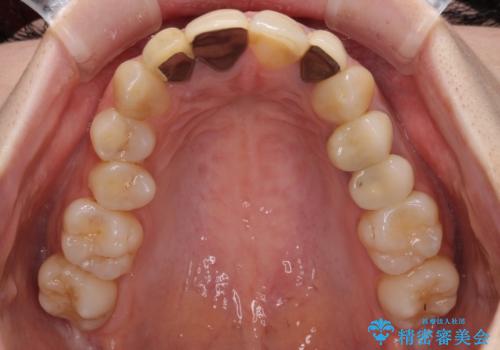

- 以前治療した前歯のクラウンの色が気になるとのことで来院された患者様です。

3歯別々に治療したクラウンは、どれも未治療の前歯を異なる色調で、口元が縞模様の印象でした。

更に、土台やフレームの金属色により、歯肉ラインが黒ずんでしまっていました。